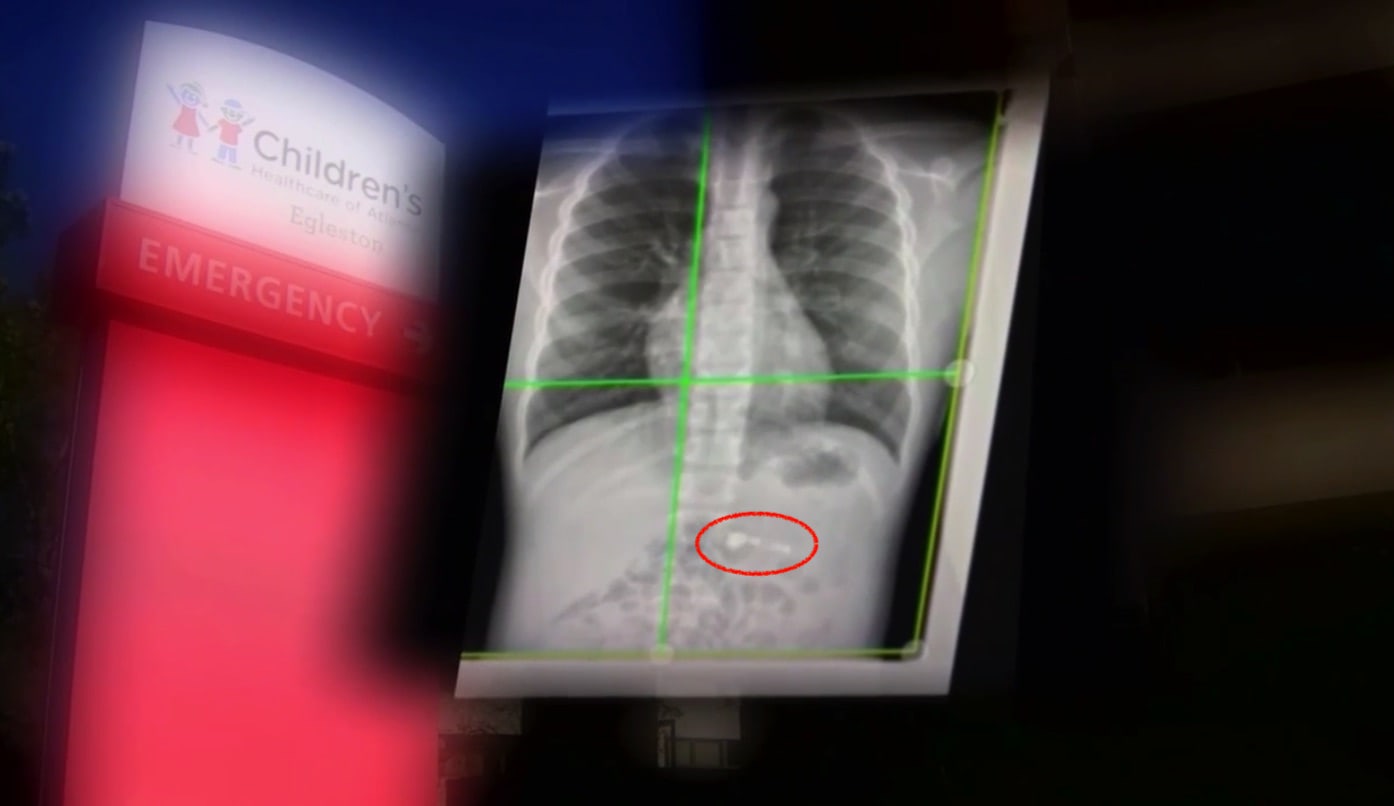

Zdá se vám první odstavec šílený? Svým způsobem je, avšak opravdu se stal. “Užila” si jej rodina z americké Georgie, ve které nadělil Santa Claus pod stromeček jejímu nejmladšímu členovi – sedmiletému chlapci, který je velký fanoušek Applu – bezdrátová sluchátka AirPods. Ten z nich byl zřejmě natolik nadšený, že se mu podařilo po pár dnech jedno ze sluchátek spolknout. To podle rentgenových snímků, které lékaři po přijetí chlapce v nemocnici kvůli chvilkové dušnosti udělali, nakonec doputovalo až pod hrudní koš, ve kterém se zastavilo.

Vzhledem k tomu, že se jedná o relativně malý předmět, se lékaři rozhodli chlapce neoperovat a jen vyčkat na to, až sluchátko vyloučí v následujících hodinách či dnech přirozenou cestou. Bohužel není ze zpráv jasné, zda si jej do té doby nechají lékaři v nemocnici pro případ jakýchkoliv potíží, či si bude chlapec moci užít čekání na druhé nadělení AirPods doma. Vcelku úsměvné je nicméně to, že hoch odmítá do chvíle, než z něj sluchátko vyjde, pohyb v blízkosti jeho iPhonu, se kterým má AirPody spárované, jelikož má strach, že by k jejich propojení došlo a sluchátko mu v břiše začalo hrát. Pokud tedy máte děti a chcete jim nadělit AirPods, nezapomeňte je minimálně důkladně proškolit o tom, že k jídlu tak úplně vhodné nejsou.